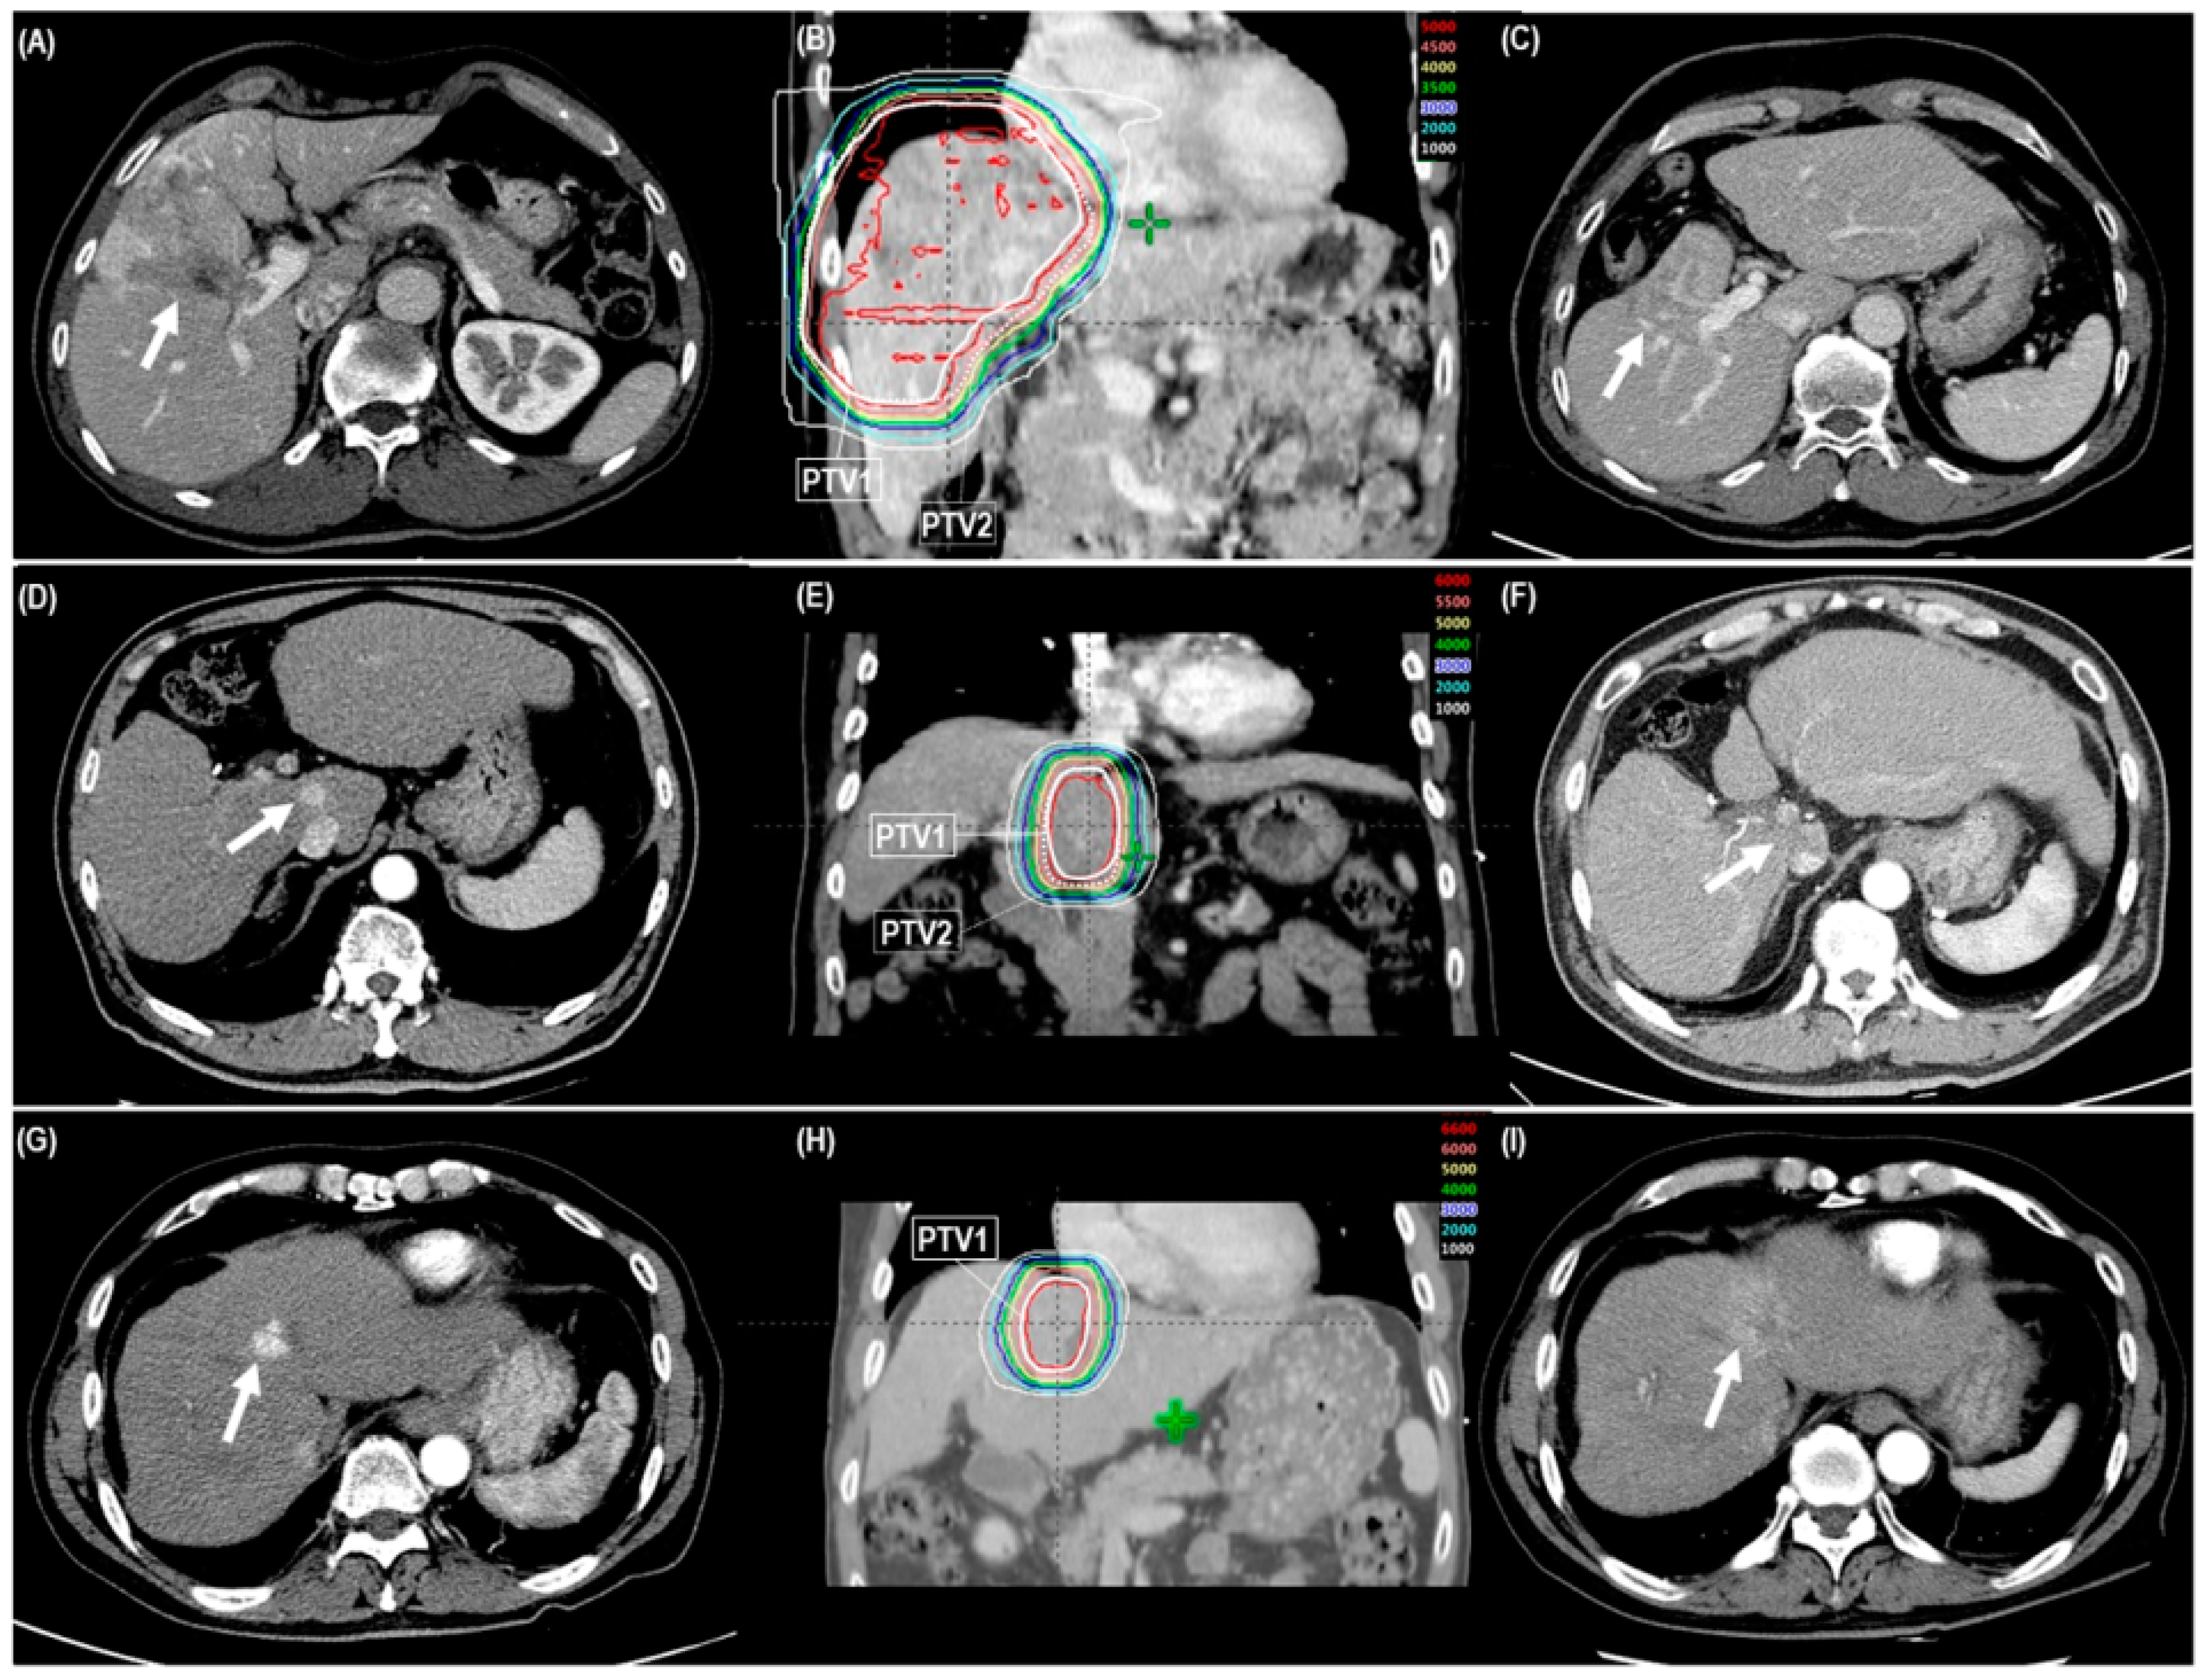

Primary tumor and TVT responses for all patients were complete response (CR) in 199 (81.9%) and 30 (50.8%), respectively; partial response (PR) in 30 (12.3%) and 18 (30.5%), respectively; stable disease in 13 (5.3%) and 10 (16.9%), respectively; and progressive disease in 1 (0.4%) and 1 (1.7%), respectively (Table 2) (Figure 1A–I). Median times to CR of the primary tumor and TVT after PBT were 4.5 months (range 1–21.7 months) and 5.1 months (range 1.1–16.4 months), respectively. The CR and objective response (CR + PR) rates of primary tumor and TVT were significantly lower in regimen A than in regimens B and C (p < 0.05 each) (Table 2). Not surprisingly, the patients who had CR less frequently received post-treatment to the PBT site than those who did not have CR (25 of 199 [12.7%] vs. 16 of 37 [43.2%], p < 0.001) (Table 2).

Figure 1.

The cases showing objective tumor response after risk-adapted proton beam therapy (PBT) with three dose-fractionation regimens (regimen A, B, and C) according to the proximity of the gastrointestinal organs (<1 cm [A–C], 1–1.9 cm [D–F], and ≥2 cm [G–I], respectively). A, D, and G: Pre-treatment computed tomography (CT) scans showing the primary tumor and/or tumor vascular thrombosis (TVT) (arrow). B, E, and H: The patient received risk-adapted PBT (50 GyE, 60 GyE, and 66 GyE in 10 fractions to PTV1, respectively, and 30 GyE in 10 fractions to PTV2). C, F, and I: One-year follow-up CT scans after risk-adapted PBT showing notable reductions of the primary tumor and/or TVT (arrow). Abbreviations: PTV, planning target volume.